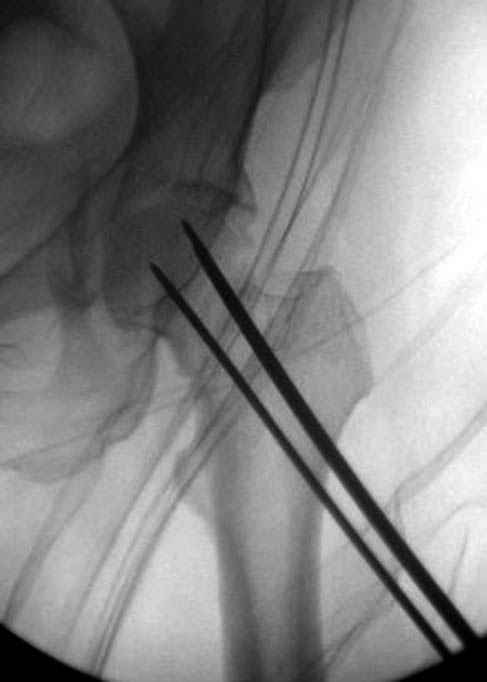

Фиксацию шейки провели когда получили окно, быстро

перкутанно смогли провести шурупы.